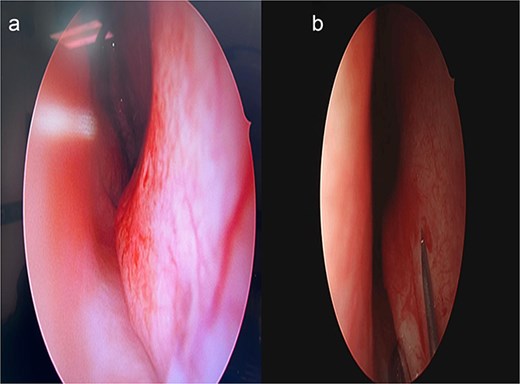

Unlike traditional techniques that require extensive septal exposure using kilian or hemitransfixasion incisions, our INES approach utilizes a targeted horizontal incision directly over the deviated from posterior to anterior (Fig. 3). Through this focused incision, superior and inferior mucosal flaps are carefully elevated, limiting the dissection to the deviated area only. This conservative approach maintains the integrity of the contralateral mucoperichondrium and preserves the surrounding normal septal architecture.

Stepwise illustration of the INES technique. (a) Deviated segment identification; (b) limited mucosal incision and flap elevation; (c) targeted resection of deviated cartilage; (d) mucosal closure without using Silastic sheets/suturing.